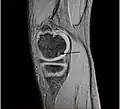

| A large flap lesion in the femur head typical of late stage Osteochondritis dissecans. In this case, the lesion was caused by avascular necrosis of the bone just under the cartilage. | |

Magnetic resonance imaging (MRI) is useful for staging OCD lesions, evaluating the integrity of the joint surface, and distinguishing normal variants of bone formation from OCD by showing bone and cartilage edema in the area of the irregularity. MRI provides information regarding features of the articular cartilage and bone under the cartilage, including edema, fractures, fluid interfaces, articular surface integrity, and fragment displacement.[37][38] A low T1 and high T2 signal at the fragment interface is seen in active lesions. This indicates an unstable lesion or recent microfractures.[30] While MRI and arthroscopy have a close correlation, X-ray films tend to be less inductive of similar MRI results.[38]

Sagittal MRI: Linear low T1 signal at the articular surfaces of the lateral aspects of the medial condyle of the femur confirms the presence of OCD. -